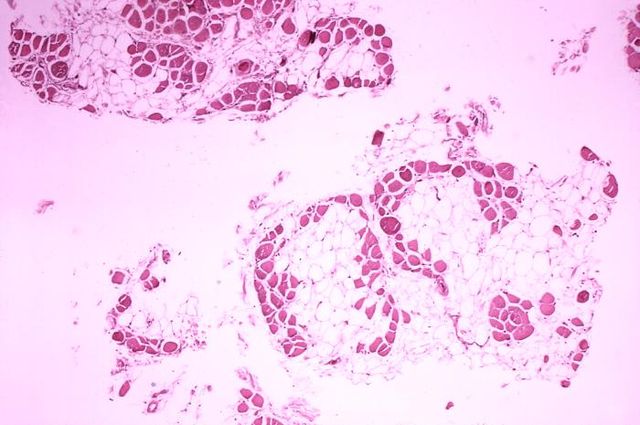

Deutsch: Histopathologisches Bild eines Querschnitts aus dem Wadenmuskel (Muskulus gastrocnemius) eines Patienten, der an Muskeldystrophie Typ Duchenne verstarb. Das Bild verdeutlicht, in welchem Ausmaß die (rot gefärbten) Muskelfasern durch Fettzellen (optisch leer = weiß) ersetzt wurden.

English: Histopathology of gastrocnemius muscle from patient who died of pseudohypertrophic muscular dystrophy, Duchenne type. Cross section of muscle shows extensive replacement of muscle fibers by adipose cells.